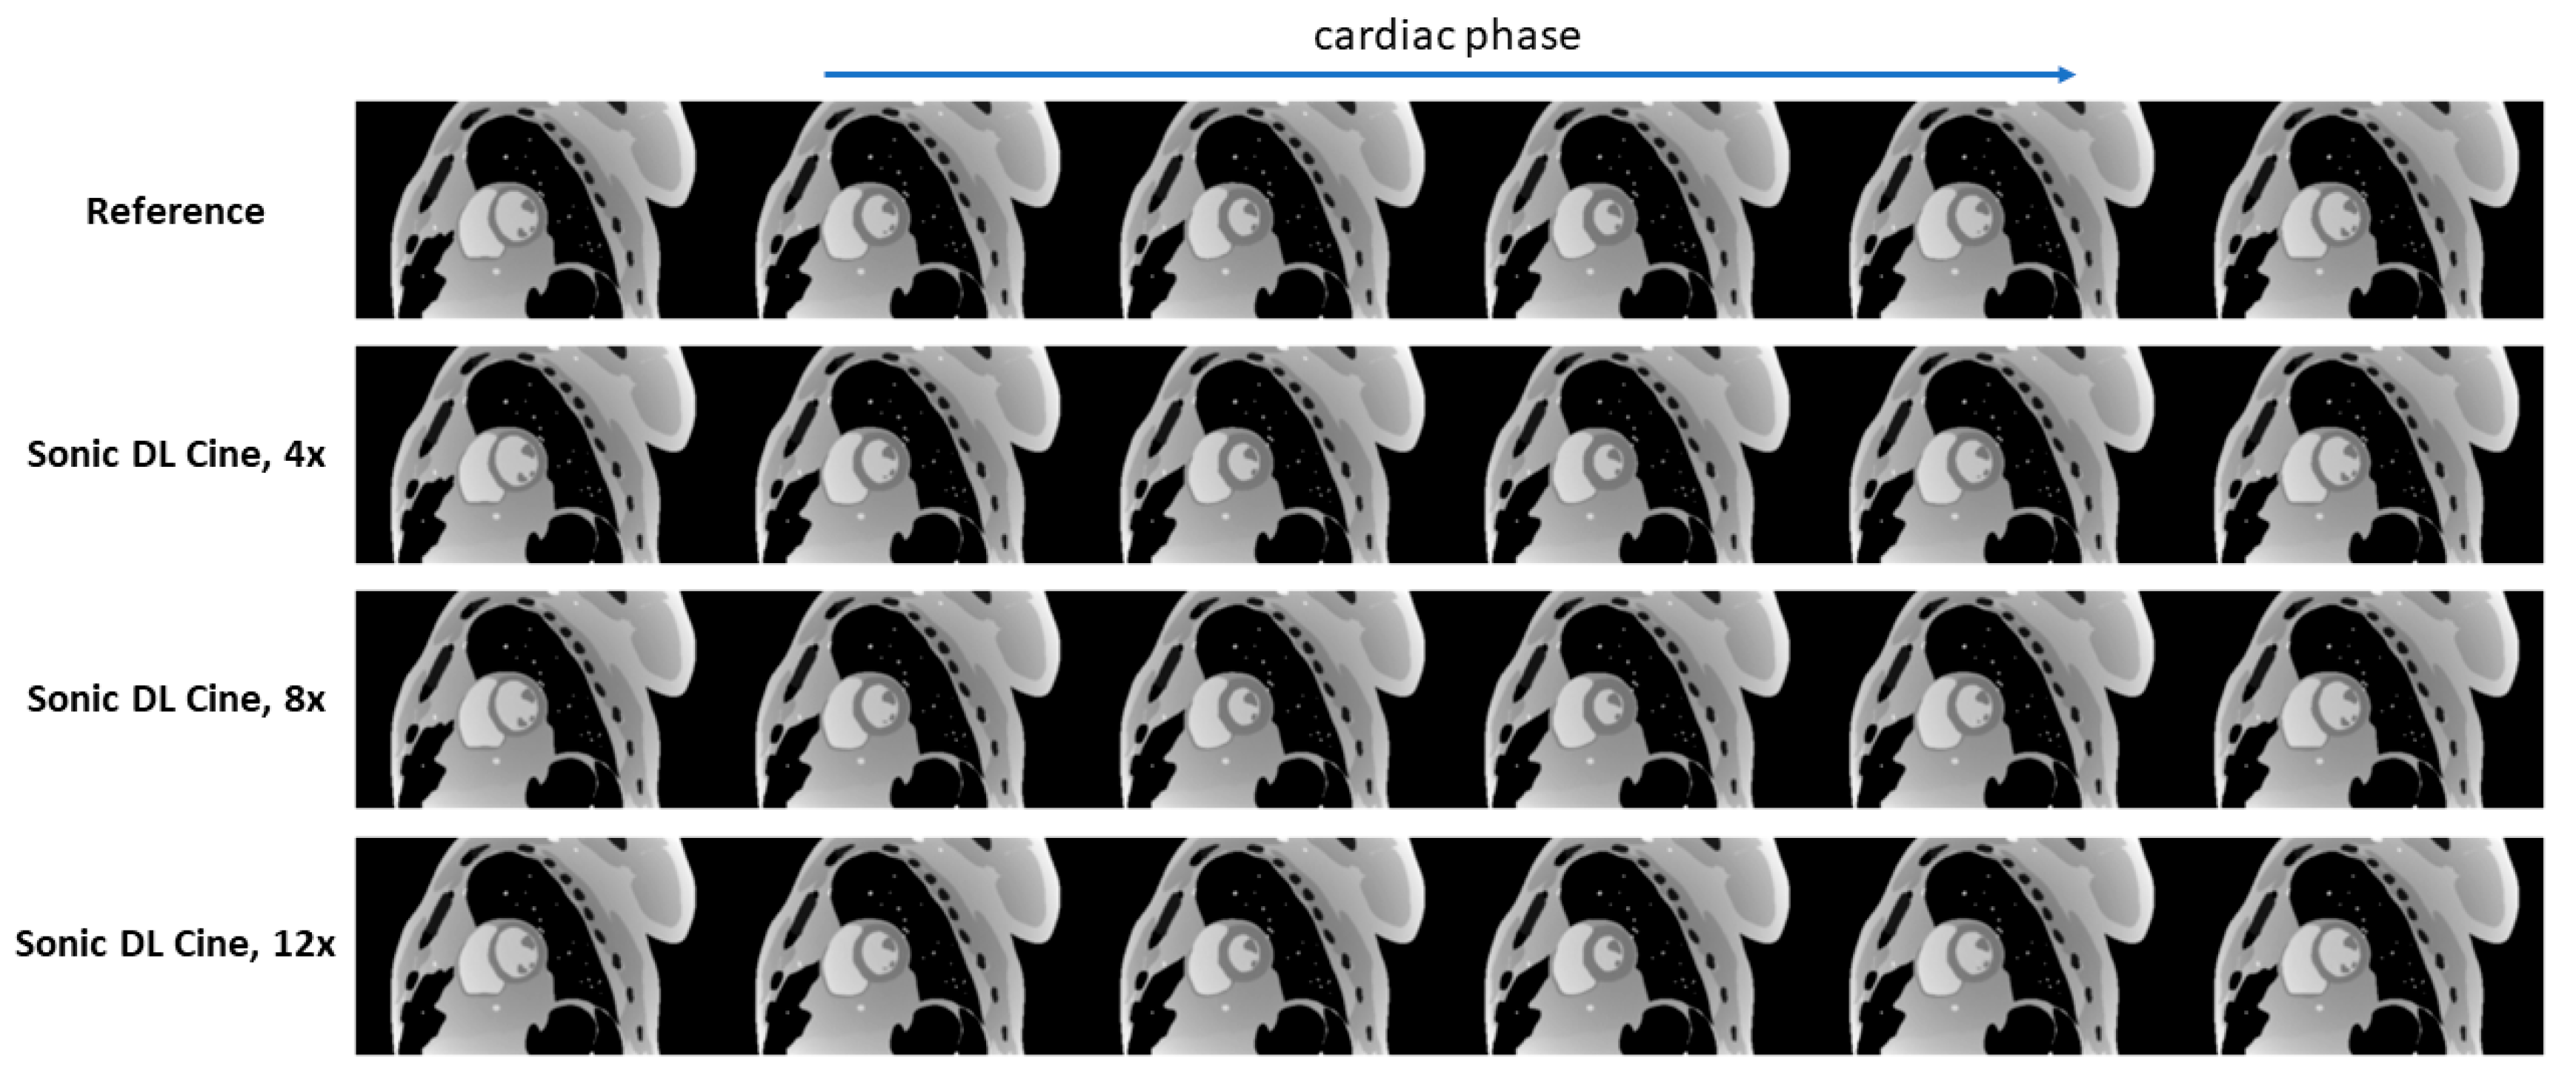

Fully sampled and Sonic DL Cine-reconstructed cine images with different acceleration factors from the digital phantom are shown in Figure 3. Sonic DL Cine images with different acceleration factors generally exhibit comparable image quality to the fully sampled reference images across various cardiac phases. No difference in image contrast or sharpness is observed visually between Sonic DL Cine and fully sampled images. The corresponding metrics, PSNR, SSIM, RMSE, and MAE, averaged from different cardiac phases are reported in Table 2. The Sonic DL Cine images overall show high PSNR, and the SSIM, RMSE, and MAE values indicate high similarity between the Sonic DL Cine and fully sampled reference images, and the similarity drops slightly with increasing acceleration factor. Signal profiles along the reference line (red dashed line in Figure 4a) in both spatial and temporal domains are shown in Figure 4. Sonic DL Cine images with acceleration factors of 4, 8, and 12 show similar temporal sharpness as the fully sampled reference images (Figure 4b). Specially, in Figure 4c, the signal profile at the end-systole phase (green dashed line in Figure 4b) shows comparable image sharpness between Sonic DL Cine and fully sampled reference images even with an acceleration factor of up to 12. These results demonstrate that Sonic DL Cine can reconstruct high-quality cine images from the under-sampled k-space data with strong generalizability and robustness, given that the model has never seen non-MR data during training.

Figure 3.

Reconstructed multi-phase cine images from the digital phantom. Multi-phase fully sampled cine images (reference) were retrospectively under-sampled by 4-fold, 8-fold, and 12-fold and reconstructed using Sonic DL Cine. PSNR, SSIM, RMSE, and MAE were calculated for images from each cardiac phase, and the mean values across different cardiac phases were reported. PSNR = peak signal-to-noise ratio; SSIM = structural similarity index measure; RMSE = root mean square error; MAE = mean absolute error.